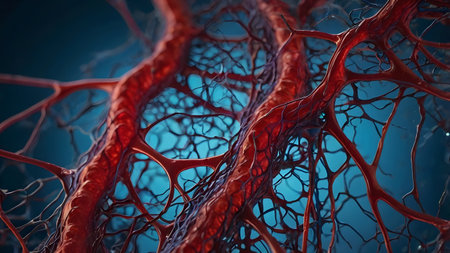

Macro view of human blood vessel network with red and blue tones showing capillaries and vein structure, ideal for illustrating medical anatomy and biology research.

Detailed visuals showcase the complex network of blood vessels in human anatomy.

A detailed view of red blood vessels intertwines across a soft gradient background. The intricate network showcases the complexity of human circulation highlighting the various sizes and shapes of the vessels

Human red blood vessels in vein close up. 3d illustration.

Vessel flow texture in red and blue lighting showing microscopic circulation system pattern symbolizing human biology, anatomy, and healthcare science visualization.

Detailed visualization of intertwined red capillaries resembling a biological network, set against a dark blue backdrop